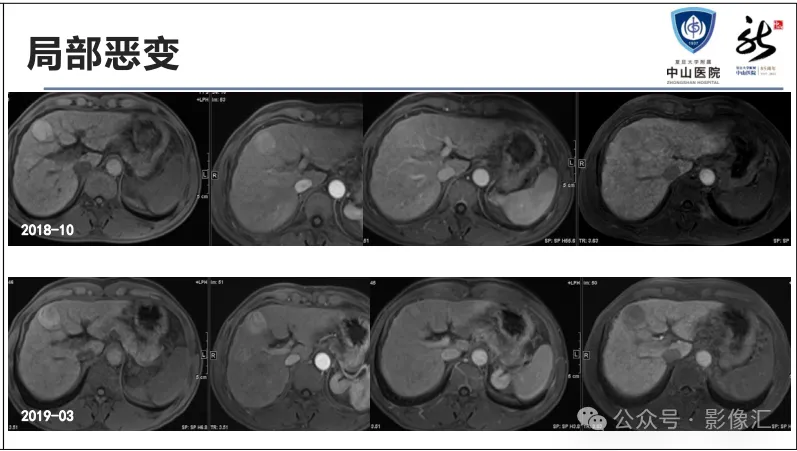

肝胆特异性对比剂增强肝胆图像判读方法与策略,课件来源于网络,作者复旦大学附属中山医院放射科饶圣祥教授。